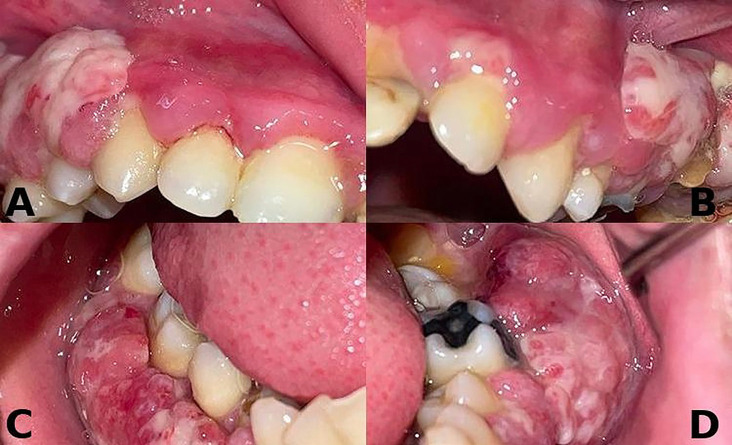

Congenital plasminogen (PLG) deficiency is an exceptionally uncommon hereditary disease associated with biallelic pathogenic / likely pathogenic variants in the PLG gene. Ligneous periodontitis (LP) is a rare disorder that can occur as a result of a lack of plasminogen. It is defined by the presence of lobulated, membranous, and ulcerated masses in the gums, as well as significant damage to the surrounding bone. This case report presents the diagnosis, treatment, and follow-up outcomes of a 23-year-old male patient who referred to our clinic with a complaint of widespread gingival enlargement. We identified a novel c.2087G>C (p.Arg696Pro) variant with a known variant detected in a compound heterozygous state in PLG confirming the molecular etiology. This case report emphasizes the importance of dentists identifying oral manifestations of various systemic diseases. Careful examination of such findings and the timely referral of patients to appropriate specialists for diagnosis and treatment are of critical significance. Key words:Ligneous periodontitis, plasminogen deficiency, genetic confirmation, histopathological diagnosis.